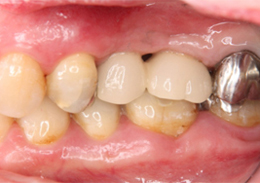

ショートインプラントの症例写真

ショートインプラント使用し骨造成をしないグラフト術式

- 主訴

- 左上ブリッジの支台であった左上5を歯根破折でばっしとなり左上56の欠損となった

- 治療内容

- 抜歯から3ヶ月の治癒期間を経てCT撮影を行った結果、通常であれば上顎洞挙上手術の対象となるケースが多いが、ショートインプラントを用いることで大規模な骨造成お回避できることがわかった。2本ショートインプラント埋入

- 治療費用

- 900,000円(税別)

- 治療期間

- 5ヶ月